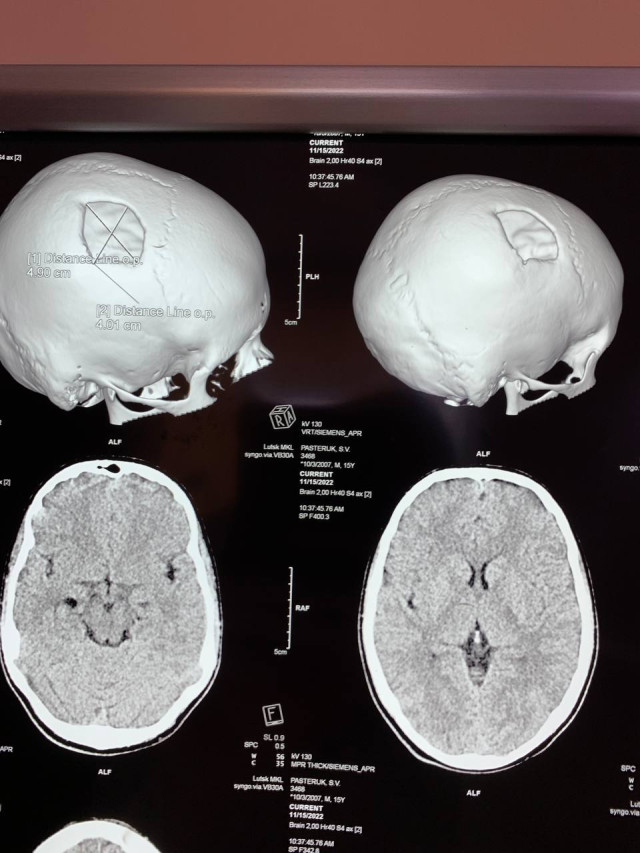

Працівники Рівненської обласної дитячой лікарні виконали краніопластику 15-річному хлопцю з Волині, який дев'ять місяців тому отримав складну черепно-мозкову травму.

Краніопластика - це хірургічна операція з усунення дефектів черепа, спричинених попередніми травмами або операціями.

Пошкоджену частину черепної коробки закрили спеціальною титановою пластиною, яка повторює кісткові структури черепа, захищає мозок від ушкоджень.

Оперативне втручання провели лікар-нейрохірург Сергій Романчук та лікар-хірург Ігор Сегін.

Операція пройшла успішно, хлопця на третю добу виписали додому.